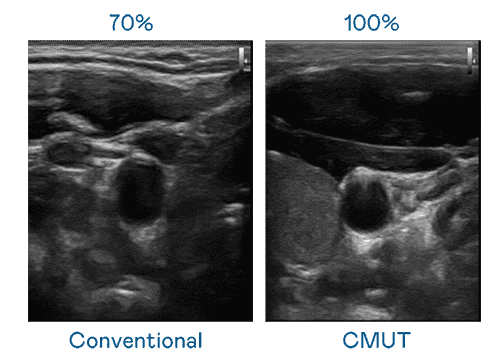

CMUT 技术是一种用电容式微机电元件来产生超音波讯号的技术。。与传统 PZT 压电式技术相比,,,CMUT 频宽增加 30%,,,更宽频的超音波讯号让影像解析度大幅提升,,,,是实现高影像品质医疗超音波扫描、、促进精准医疗发展的关键技术。。。。

大频宽带来超清晰影像

超音波影像的解析度高低,,,,首先取决于探头能发出的讯号频宽。。。赏金国际 CMUT 可提供高清晰的超音波讯号,,,,提供高频宽、、、、高灵敏度、、影像纹理细节更高的超音波影像,,,协助医护人员缩短影像判读时间及利用精准的医疗影像进行诊断。。